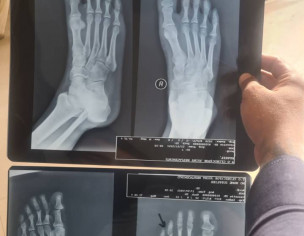

I had a fracture in my right foot thumb and i consulted a doctor they tried to set the bone and then advised me to place the foot kn cold water, then a week later om yesterday i went to have my xray done again and there is no change. Pain is still the same. And the bone i see in the xray is also same. Doctors said that the tissies are damaged and once the swelling is over the bone will be on its place. Please advise if this is gonne be okay on its own or should i get the bone fixed again Above xray is latest and below xray is a week before

This is actually not clear to see in x-rays. However, as per your indicator, it seems to fracture of middle phalanx of the 4th toe. it is usually treated with buddy strapping/immobilization. It takes about 2-3 weeks to relieve swelling. Don't put it into cold water but do icing or cold therapy and take simple painkillers to ease your pain. It will heal. Inshallah. Get consult with your same doctor again in 2 weeks if the problem doesn't resolve.